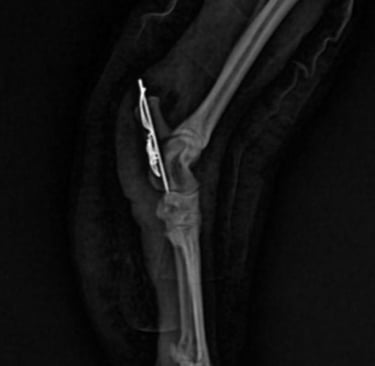

Cirurgias

Procedimentos realizados com precisão para recuperação eficaz.